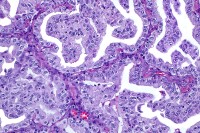

Photo of the bispecific antibody CD20xCD3 in action against a Lymphoma cell

MSK ASH 2023 Insights: Promising Results for Bispecific Antibodies as First-Line Therapies for Patients with Follicular and B Cell Lymphoma

Bispecific antibodies bind to two antigens or two parts of the same antigen at the same time. The U.S. Food and Drug Administration (FDA) recently approved two CD20xCD3 bispecific antibodies —mosunetuzumab (mosun) for patients with relapsed or refractory follicular lymphoma and glofitamab (glofit) for patients with relapsed or refractory diffuse B cell lymphoma (DLBCL) or large B cell lymphoma (LBCL) treated with two or more prior lines of therapy.